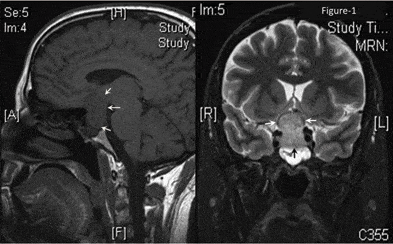

अगला चरण मस्तिष्क की इलेक्ट्रिकल गतिविधि और रक्त प्रवाह की असामान्यताओं को देखने के लिए परीक्षण होगा। आपका डॉक्टर एक या इन टेस्ट का कॉम्बिनेशन टेस्ट करने के लिए बोल सकता है –

मेग्नेटिक रेसोनेंस इमेजिंग (एमआरआई) – इस तकनीक में मेग्नेटिक फील्ड और रेडियो तरंगो का इस्तेमाल किया जाता है जिसमें विस्तृत जानकारी, मस्तिष्क की क्रॉस सेक्शनल इमेज का पता चलता है। एमआरआई मशीन इन टुकड़ों वाली इमेजों को जोड़ता है और 3डी इमेजो में दिखाता है जिसे अलग-अलग एंगल से देखा जा सकता है।

कम्पूटराइड टोमोग्राफी (सीटी) – ख़ास एक्सरे उपकरणों के इस्तेमाल से, आपका डॉक्टर अलग-अलग एंगल से इमेज को दिखाएगा और उन्हें जोड़कर मस्तिष्क और स्कल की क्रॉस सेक्शनल इमेज को दर्शाएगा। सीटी स्कैन मस्तिष्क की संरचना में असामान्यताओं को दिखा सकता है, जिसमें संकुचित, अतिरंजित या टूटी हुई रक्त वाहिकाएं और पिछले स्ट्रोक शामिल हैं।